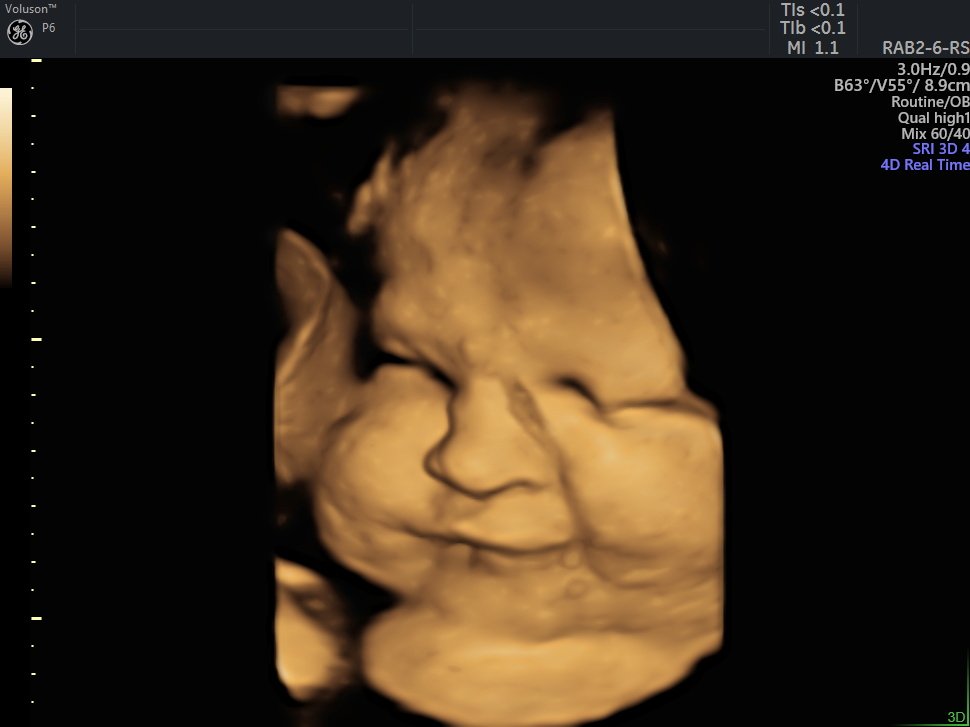

4 D Ultrasonografi

4 Boyutlu (Renkli) Ultrason ve Doppler Ultrasonografi